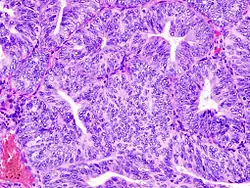

(A) proliferative endometrium (Left: HE × 400) and proliferative endometrial cells (Right: HE × 100)

(B) secretory endometrium (Left: HE × 10) and secretory endometrial cells (Right: HE × 10)

(C) atrophic endometrium (Left: HE × 10) and atrophic endometrial cells (Right: HE × 10)

(D) mixed endometrium (Left: HE × 10) and mixed endometrial cells (Right: HE × 10)

(E): endometrial atypical hyperplasia (Left: HE × 10) and endometrial atypical cells (Right: HE × 200)

(F) endometrial carcinoma (Left: HE × 400) and endometrial cancer cells (Right: HE × 400).

Chorionic tissue can result in marked endometrial changes, known as an Arias-Stella reaction, that have an appearance similar to cancer.[15] Historically, this change was diagnosed as endometrial cancer and it is important only in so far as it should not be misdiagnosed as cancer.

- Adenomyosis is the growth of the endometrium into the muscle layer of the uterus (the myometrium).

- Endometriosis is the growth of tissue similar to the endometrium, outside the uterus.[16]

- Endometrial hyperplasia

- Endometrial cancer is the most common cancer of the human female genital tract.

- Asherman's syndrome, also known as intrauterine adhesions, occurs when the basal layer of the endometrium is damaged by instrumentation (e.g., D&C) or infection (e.g., endometrial tuberculosis) resulting in endometrial sclerosis and adhesion formation partially or completely obliterating the uterine cavity.